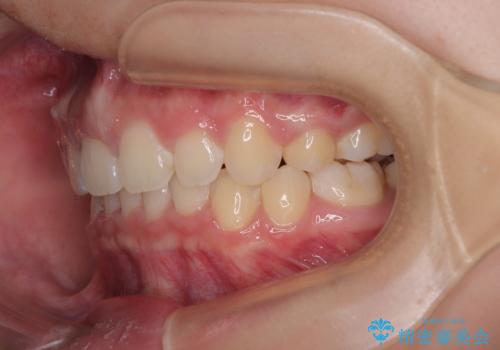

- 上顎前歯が飛び出していて唇がうまく閉じられないとのことで来院された患者様です。

くちばしのように前歯が突出していたため、口元を積極的に引っ込めるために、上下左右の小臼歯4本を抜歯することとしました。

また、上顎歯列が下顎に対して前方位に位置していたため、補助装置を用いて上顎歯列を後方に移動させ、より積極的に口元を下げるようにしました。